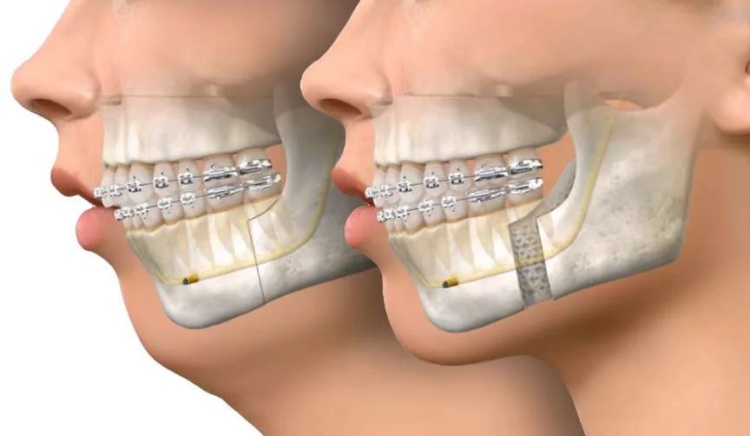

شكل الوجه (توازن أفضل)

قبل جراحة الفكين قد يبدو شكل الوجه غير متناغم، مثل بروز الفك العلوي أو السفلي، أو الذقن المتراجع، أو عدم تناسق جانبي بين الجهتين.

بعد جراحة الفكين في جدة، يعمل جراح الفكين على إعادة وضع الفك العلوي والسفلي في موضعهما الصحيح، مما يحسّن توازن ملامح الوجه ويمنح المريض شكلًا أكثر تناسقًا وجاذبية من الأمام والجانب.

هذه التغييرات في شكل الوجه بعد جراحة الفكين لا تهدف فقط لتحسين المظهر الجمالي، بل تساعد أيضًا في تصحيح مشكلات وظيفية مرتبطة بالمضغ والنطق والتنفس، ما يجعل النتائج قبل وبعد جراحة الفكين تغييرًا شاملًا في الشكل والأداء معًا.

هل جراحة الفكين تغيّر شكل الوجه بشكل كبير؟

نعم، يمكن أن تغيّر جراحة الفكين شكل الوجه بشكل ملحوظ وإيجابي، لكنها تتم بطريقة مدروسة لتحقيق توازن جمالي ووظيفي مع ملامح الوجه الطبيعية.

تعالج جراحة الفكين في جدة مشكلات بروز أو تراجع الفك، عدم تطابق الأسنان، بروز الذقن أو صغرها، ومشكلات الابتسامة اللثوية، ما ينعكس مباشرة على شكل الفك السفلي والعلوي والوجنتين والذقن.

يقوم جرّاح الفكين بدراسة دقيقة للوجه باستخدام صور شعاعية ثلاثية الأبعاد وتحاليل عضوية لتحديد مقدار التعديل المطلوب، بحيث يكون التغيير متناسقًا ولا يبدو مصطنعًا.

في أغلب الحالات، يلاحظ المريض تحسنًا واضحًا في تناسق ملامح الوجه، وبروز الابتسامة، وتصحيح انحراف الفك، مع الحفاظ على هويته الشكلية دون تغيير جذري مبالغ فيه.